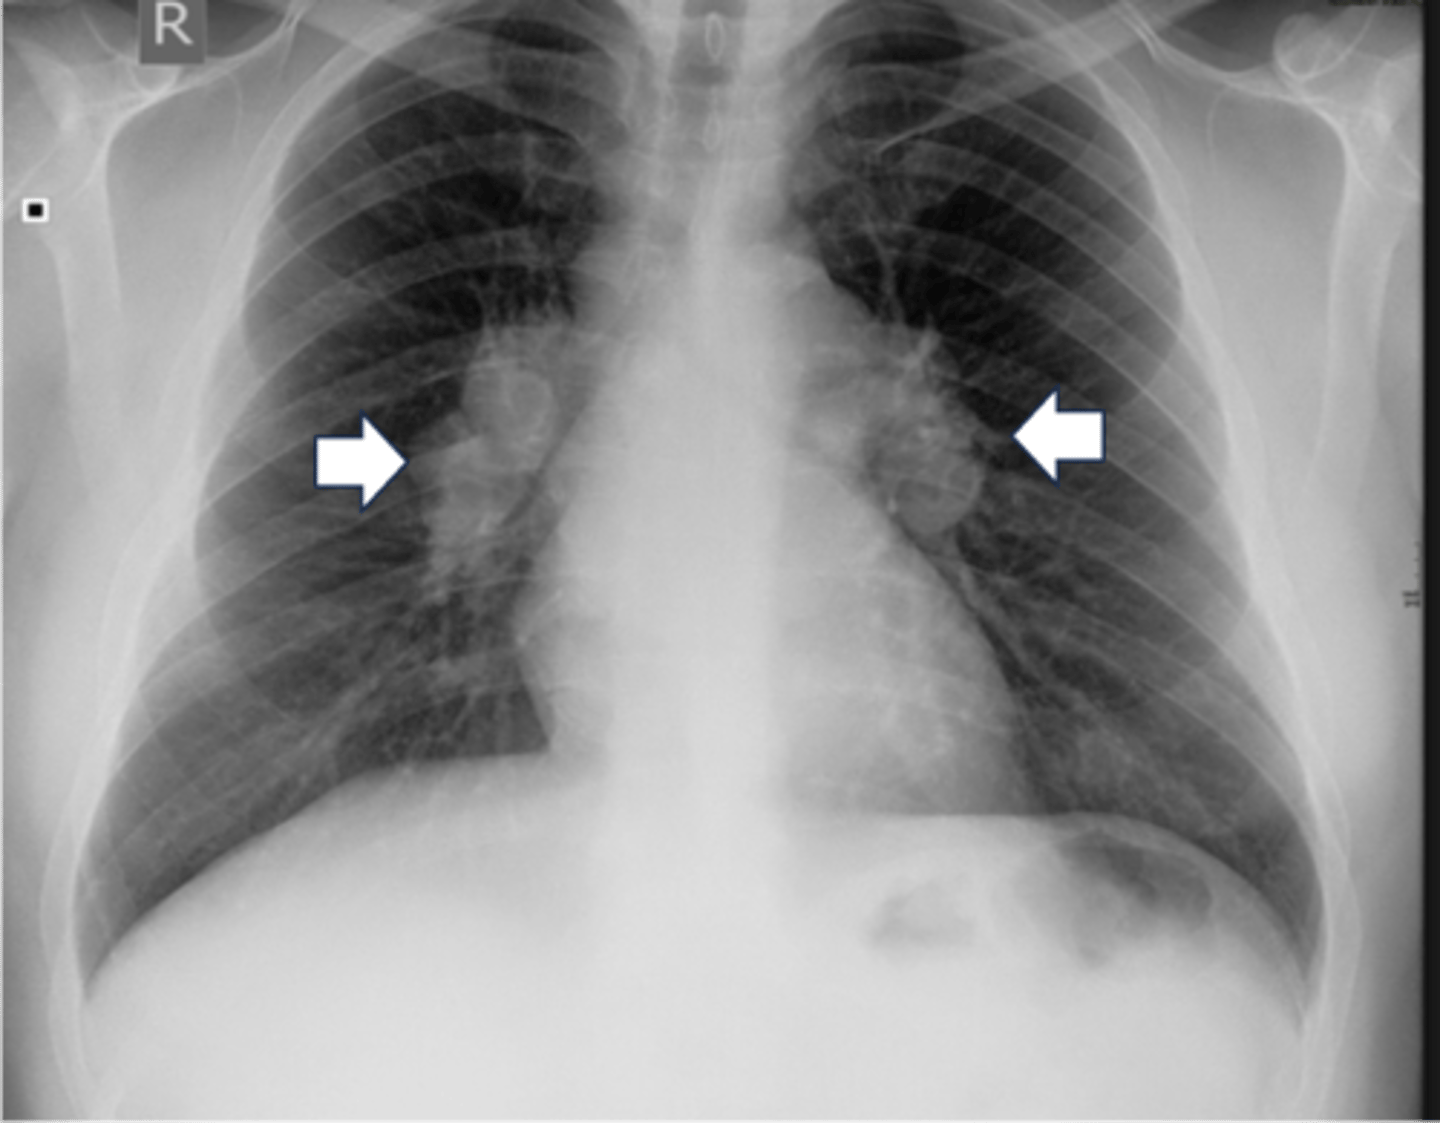

-look for nodes or vasculature on the hila of both lungs

-left hila should be higher

H: Hila

-TB or sarcoidosis

What does bilateral hilar enlargment suggest

cancer

What does unilateral hilar enlargment suggest

white mass in hilar area

Hilar adenopathy appearance